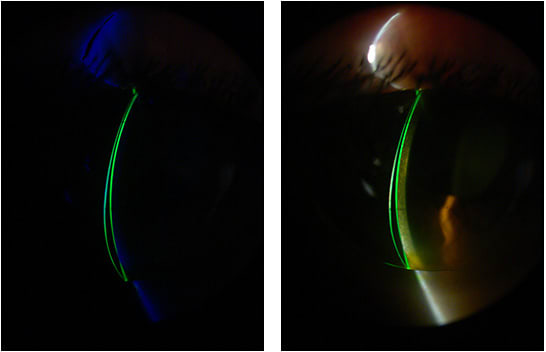

During his first examination in 2009, this patient was wearing a flat lens that had a poor peripheral fit, and his eyes presented severe hyperemia. He was instructed to suspend lens wear for three days and to return for a follow-up exam and contact lens evaluation. Figure 2 shows the trial intralimbal lens over the cornea, with several areas of superficial keratitis from the previous lens. He had stopped wearing a lens on this eye just one day prior to the first visit.

The intermediate curve of a 9.5mm diameter GP lens is thinner compared to a large intralimbal diameter of 12.5mm, but it would decenter during blinking, leading to awareness and dislocating the central optics, affecting vison. Figure 3 shows the aspheric-front-surface design with a plus flange.

We schedule three follow-up evaluations for first-time GP lens patients within 10, 30, and 90 days from the dispensing day. This is time enough to make adjustments to the fit and also to prevent interruption of the adaptation process. Figure 4 shows the final lens dispensed to the patient in higher magnification with a cobalt blue filter and fluorescein. A video of the fit is available below.